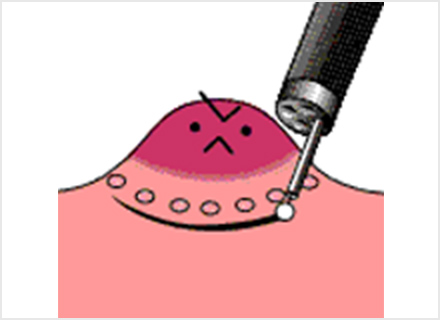

内視鏡的粘膜下層剥離術:ESD(Endoscopic submucosal dissection)

専用の処置具を使いより広範囲に病変を切り取ることが可能な治療法です。切り取られた病変は、最終的に顕微鏡でその組織の様子が確認されます(病理検査)。この方法では、大きな病変をひとかたまりで取り、病理検査でより正確な診断を行うことができます。

ESDは大きな病変も一括して切除可能ですが、手技が煩雑で時間がかかり、出血や穿孔などの併発症が生じる場合があります。ほとんどの場合内視鏡的に止血可能ですが、稀には輸血、開腹手術などを要することがあります。

内視鏡を胃の中に入れ、病変の周辺に切り取る範囲の目印をつける

粘膜下層に薬剤を注入して浮かせた状態にする

マーキングを切り囲むようにナイフで病変部の周囲の粘膜を切る

専用ナイフで病変を少しずつ慎重にはぎ取る

ナイフを使って最後まで剥離する、またはスネアで切り取る

切り取った後の胃の表面に止血処置を施し、切り取った病変部は病理検査に出すために回収する

切り取った病変は顕微鏡による組織検査をして、根治しているかの判断をする

※オリンパス社ホームページ おなかの健康ドットコム より引用